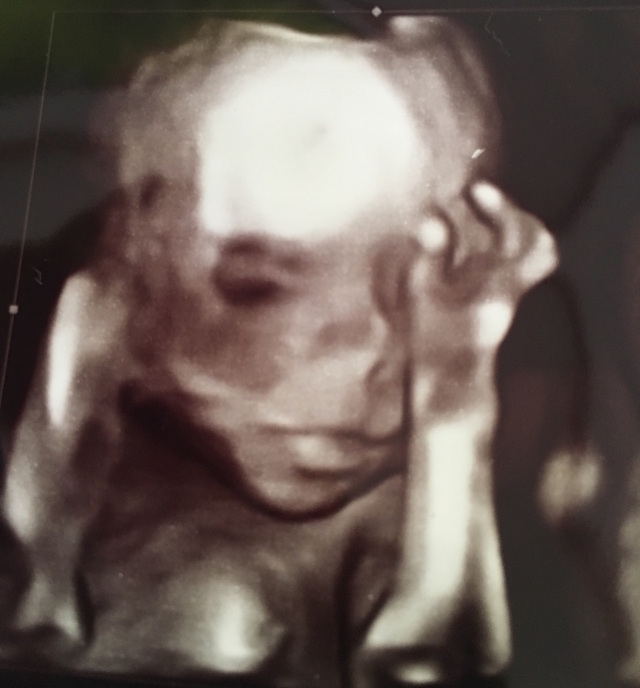

22週3日(22w3d・女の子)|baby0922 さん(27歳)

エコー写真撮影時のエピソード:

安定期に入り、エコーでも顔が結構分かるようになってきた頃でした。

私が安定期に入ったのは春〜初夏だったのでたくさんお散歩をしていました。

水分をたくさんとったり、栄養も葉酸の多いものや野菜をたくさん摂るように心がけていました。

エコーはぱっちりこちらを向いていて驚いた思い出の一枚です。

こんなにホラーのような写真が撮れると思わなかったのでとても面白く、笑ったのを覚えています。

お腹の中で目があったような気持ちになり、嬉しかったです!